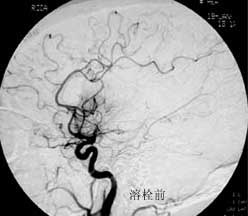

三、闭塞性脑血管病

----闭塞性脑血管病,如急性脑梗塞引起的偏瘫、颈动脉或椎基底动脉狭窄所致短暂性脑缺血发作(TIA)及可逆性神经 功能障碍(RIND),视网膜中央动脉或中央静脉闭塞引起的视力减退,静脉窦血栓性形成引起的颅内压增高等,均可通过 血管内的介入治疗得以改善,介入治疗的方法分溶栓、血管成形术或支架置入,根据病变选择不同的治疗方法。

2.急性梗塞动脉内接触性溶栓治疗的适应证:

(1)发病6小时内;

(2)CT或MEI检查没有梗塞及出血表现;

(3)对大脑中动脉卒中者,133XESPECT检查显示CBF残存超过每分钟15ml/100g;

(4)血管造影证实颅内血栓及部位;

(5)基底动脉溶栓可延至发病后48小时。

3.视网膜中央动脉闭塞的动脉内溶栓治疗适应证:

(1)视力突然下降或丧失后6小时内;

(2)超选动脉造影显示视网膜中央动脉闭塞。据北京医院介入神经放射学研究中心的经验,尽管动脉内溶栓在发病后超过 6小时(8-14)实施,术中眼底检查,可视网膜供血情况好转,部分病例溶栓治疗结束时,视力即有改善,还有部分病例术 后1个月随访时,视力仍有改善。